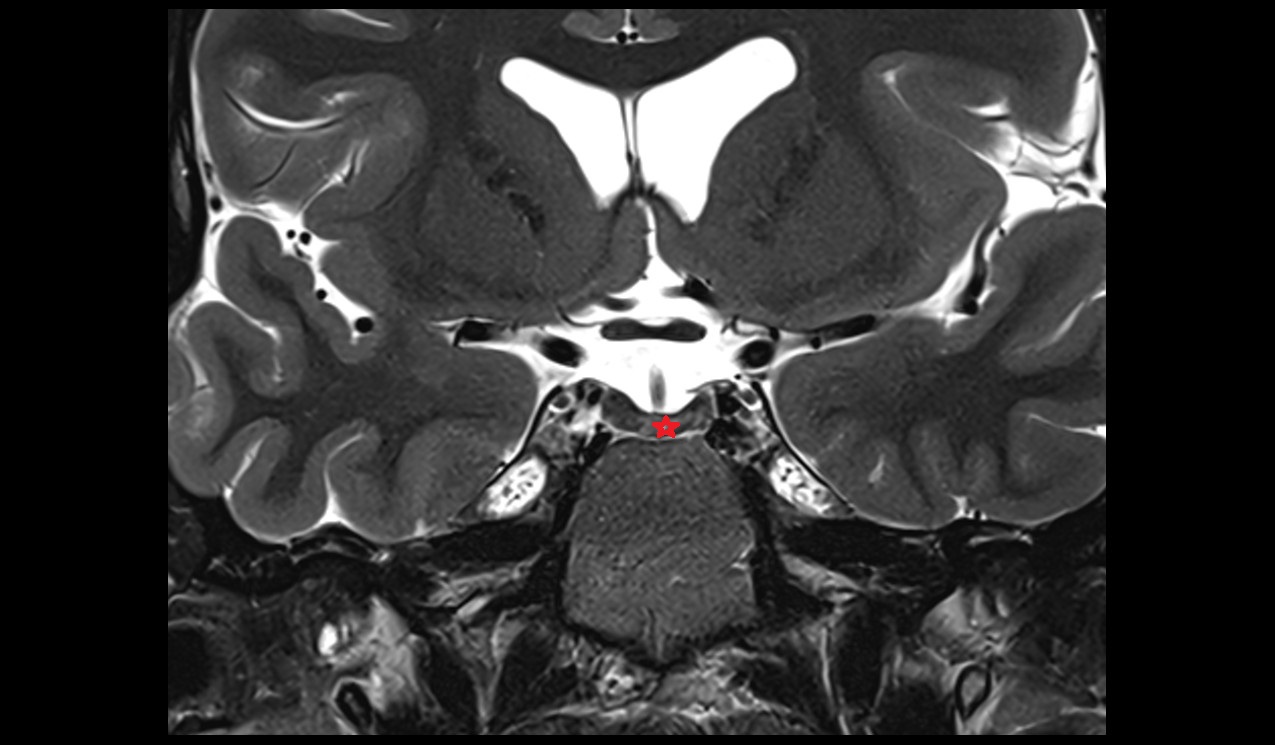

- Peripheral zone of prostate

- Anterior Fibromuscular Stroma of prostate

- Central zone of prostate

- Transitional zone of prostate

- Membranous urethra

- Prostatic urethra

- Penile urethra